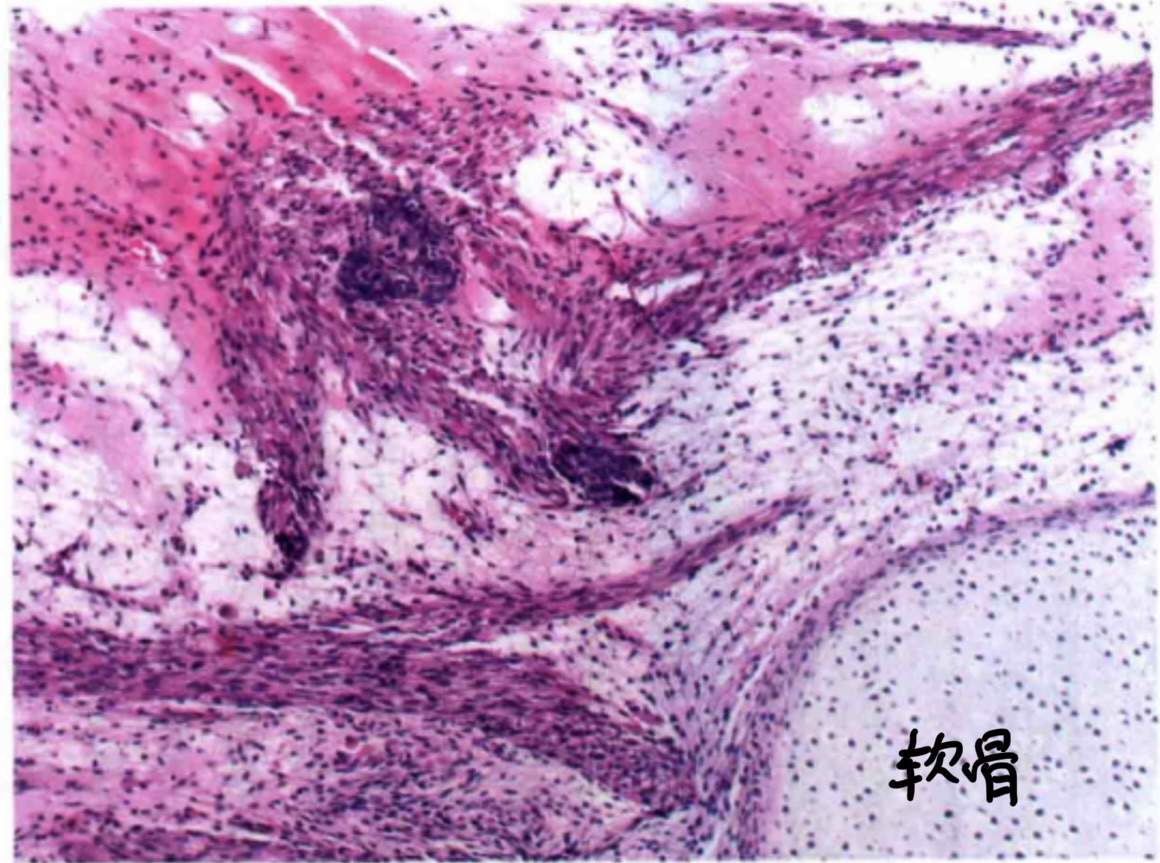

其次,中低分化时可有异源性成分(例如:黏液腺体/类癌细胞横纹肌/灶状软骨等)和(或)网状成分

最后,它有个特殊类型:网状型Sertoli-Leydig细胞肿瘤,如图:

不规则分枝状,细长,狭窄,常呈裂隙样。